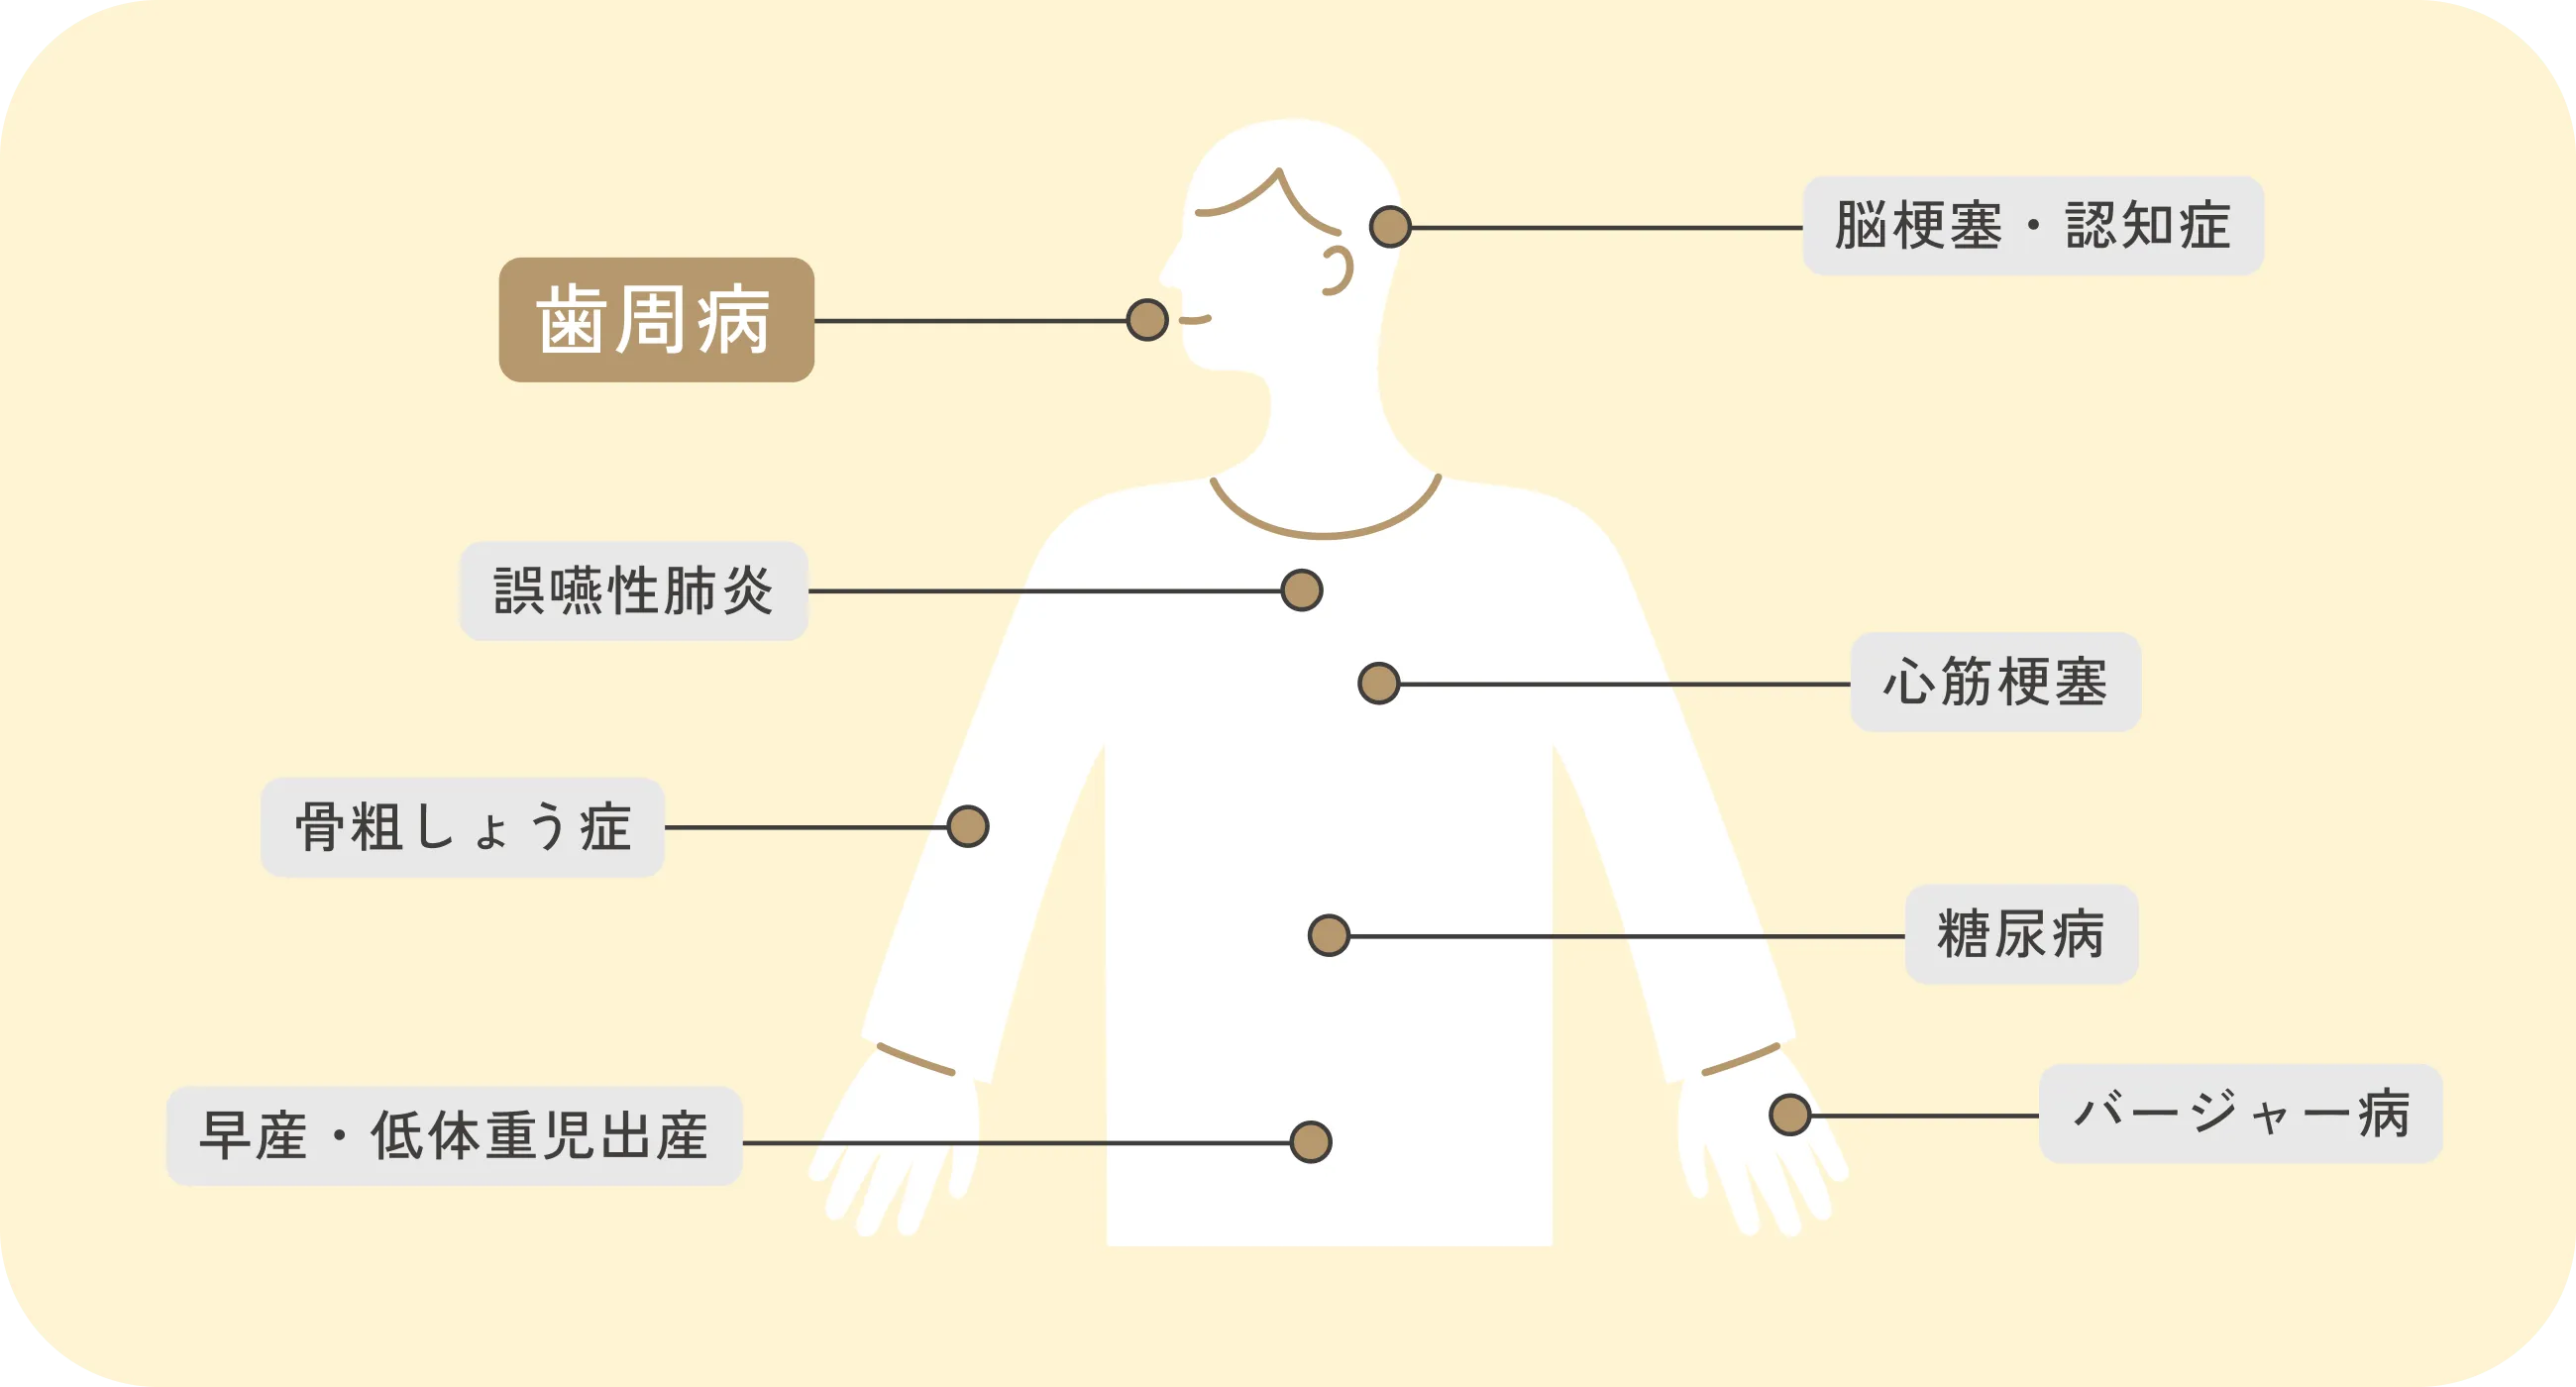

お口の中で増えた歯周病菌やその毒素が血流を通じて全身に影響を及ぼし、心疾患や脳疾患、糖尿病の悪化、認知症、誤嚥性肺炎などのリスクを高めることがわかっています。さらに、妊婦の場合「早産」や「低体重児出産」のリスクが高まるという報告もあります。お口の健康は全身の健康に密接に関わっているため、歯周病予防/治療はとても大切です。